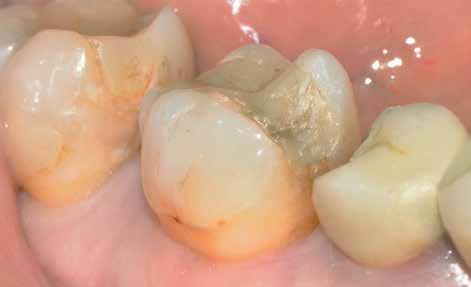

Abban az esetben, ha előrehaladott állapotban lévő fogágybetegség kezelését végezzük, azaz 5 mm-es, vagy annál nagyobb tasakmélységet mértünk, akkor a számunkra kívánatos változások elérése érdekében egy második tisztítási fázis elvégzésére is szükség van. Ehhez egy 980 nm-es hullámhosszon, 10 W-os teljesítmény mellett alkalmazott diódalézert is használhatunk, amely nem csak szájsebészeti célú alkalmazásra, hanem a parodontális elváltozások kezelésére is alkalmas lehet.

A második szakaszban a protokollnak megfelelően végzett kezelés során egy PRIMO diódalézert (MEDENCY, 9. ábra) alkalmazunk. A beavatkozás során 10 mm hosszú 400 μ széles, egyszer használatos fényvezető szálakat használunk. A készüléket az alábbi paramétereknek megfelelően állítjuk be: pulzus modalitás 30/70; 2,4 W teljesítmény; 25 másodperc működési idő. Ezek a beállítások szükségesek ahhoz, hogy a gyökérfelszínt nagy mélységben is meg tudjuk tisztítani, és a

9. ábra: A PRIMO lézerkészüléket kezelés második szakaszában, a mély parodontális tasakok ellátása során alkalmazzuk. 10. a–b ábrák: A lézerkészülék beállításai a gyökérfelszín tisztítása és a gyulladásos szövetek eltávolítása során alkalmazott paramétereknek megfelelően. 12. ábra: A 10%-os povidon-jód oldattal feltöltött tasakba bevezetésre kerülő fényvezető szál. 11. ábra: A PRIMO lézerkészülék beállításai a fájdalomcsillapító hatással járó kezelés során alkalmazott paramétereknek megfelelően.

tasak belső falán lévő gyulladásos sarjszövetek eltávolításra kerüljenek (10. a–b ábra)